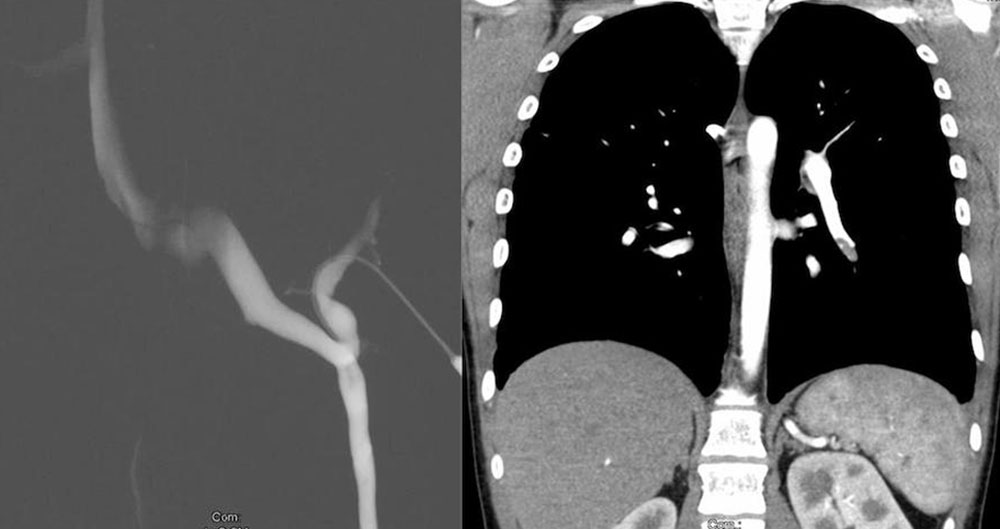

Visualization of large-lumen communicating veins from the venous malformation into the deep venous system is particularly important, since this determines not only the risk of thromboembolism, but also the effectiveness of sclerosing treatment. The focus is on vascular imaging, therefore the administration of contrast agents is always necessary. In view of the slow blood flow in a venous malformation, the late phase, also called the venous phase, should be recorded. The venous malformation is usually not visualized until after the regularly developed venous system.

High spatial resolution, good soft tissue contrast, three-dimensional image reproduction and development of specific examination protocols for tissue perfusion and vascular imaging render MRI the gold standard in venous malformation imaging. There is an indication for this if the congenital vascular malformation is extensive and/or painful, i.e., whenever invasive treatment is considered. However, findings of little clinical relevance do not require this type of diagnostic study. In particular, children should not receive unnecessary examinations under anesthesia if invasive therapy is not being considered. In addition to the justifying indication, appropriate know-how in the selection of image sequences is essential for the success of the examination. In a team discussion between clinicians and radiologists, the relevant questions should be clarified, and the appropriate protocol should be chosen. The examination is performed without and with contrast medium as magnetic resonance angiography (MRA), so that the venous malformation can be distinguished from an LM, since the latter does not enhance. A venous malformation is strongly hyperintense (white) in the T2-weighting, especially after fat suppression. In the native T1-weighted images it is hypointense, similar to musculature. After administration of contrast medium it shows slow but almost complete enhancement of the lesion.

Computed tomography (CT)

This sectional imaging technique provides three-dimensional images with a spatial resolution comparable to that of MRI, but with the disadvantage of radiation exposure and lower soft tissue contrast. Accordingly, it is generally only used when there are contraindications to MRI (claustrophobia, non-MRI-compatible metal implants). The venous malformation is isodense to musculature and enhances entirely with the contrast medium. Calcified phleboliths are easily detected in CT.